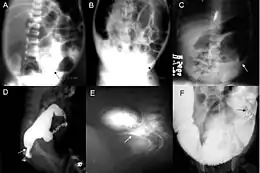

Radiologic findings may also assist with diagnosis.[29] Cineanography (fluoroscopy of contrast medium passing anorectal region) assists in determining the level of the affected intestines.

-

Barium enema in neonate with Hirschsprung disease -

A: Plain abdominal radiograph showing a PARTZ at rectosigmoid, arrow. B: Plain abdominal radiograph showing a PARTZ at midsigmoid, arrow. C: Plain abdominal radiograph showing a PARTZ at descending colon, arrow. D: Contrast enema showing a CETZ at rectosigmoid, arrow. E: Contrast enema showing a CETZ at midsigmoid, arrow. F: Contrast enema showing a CETZ at descending colon, arrow. -